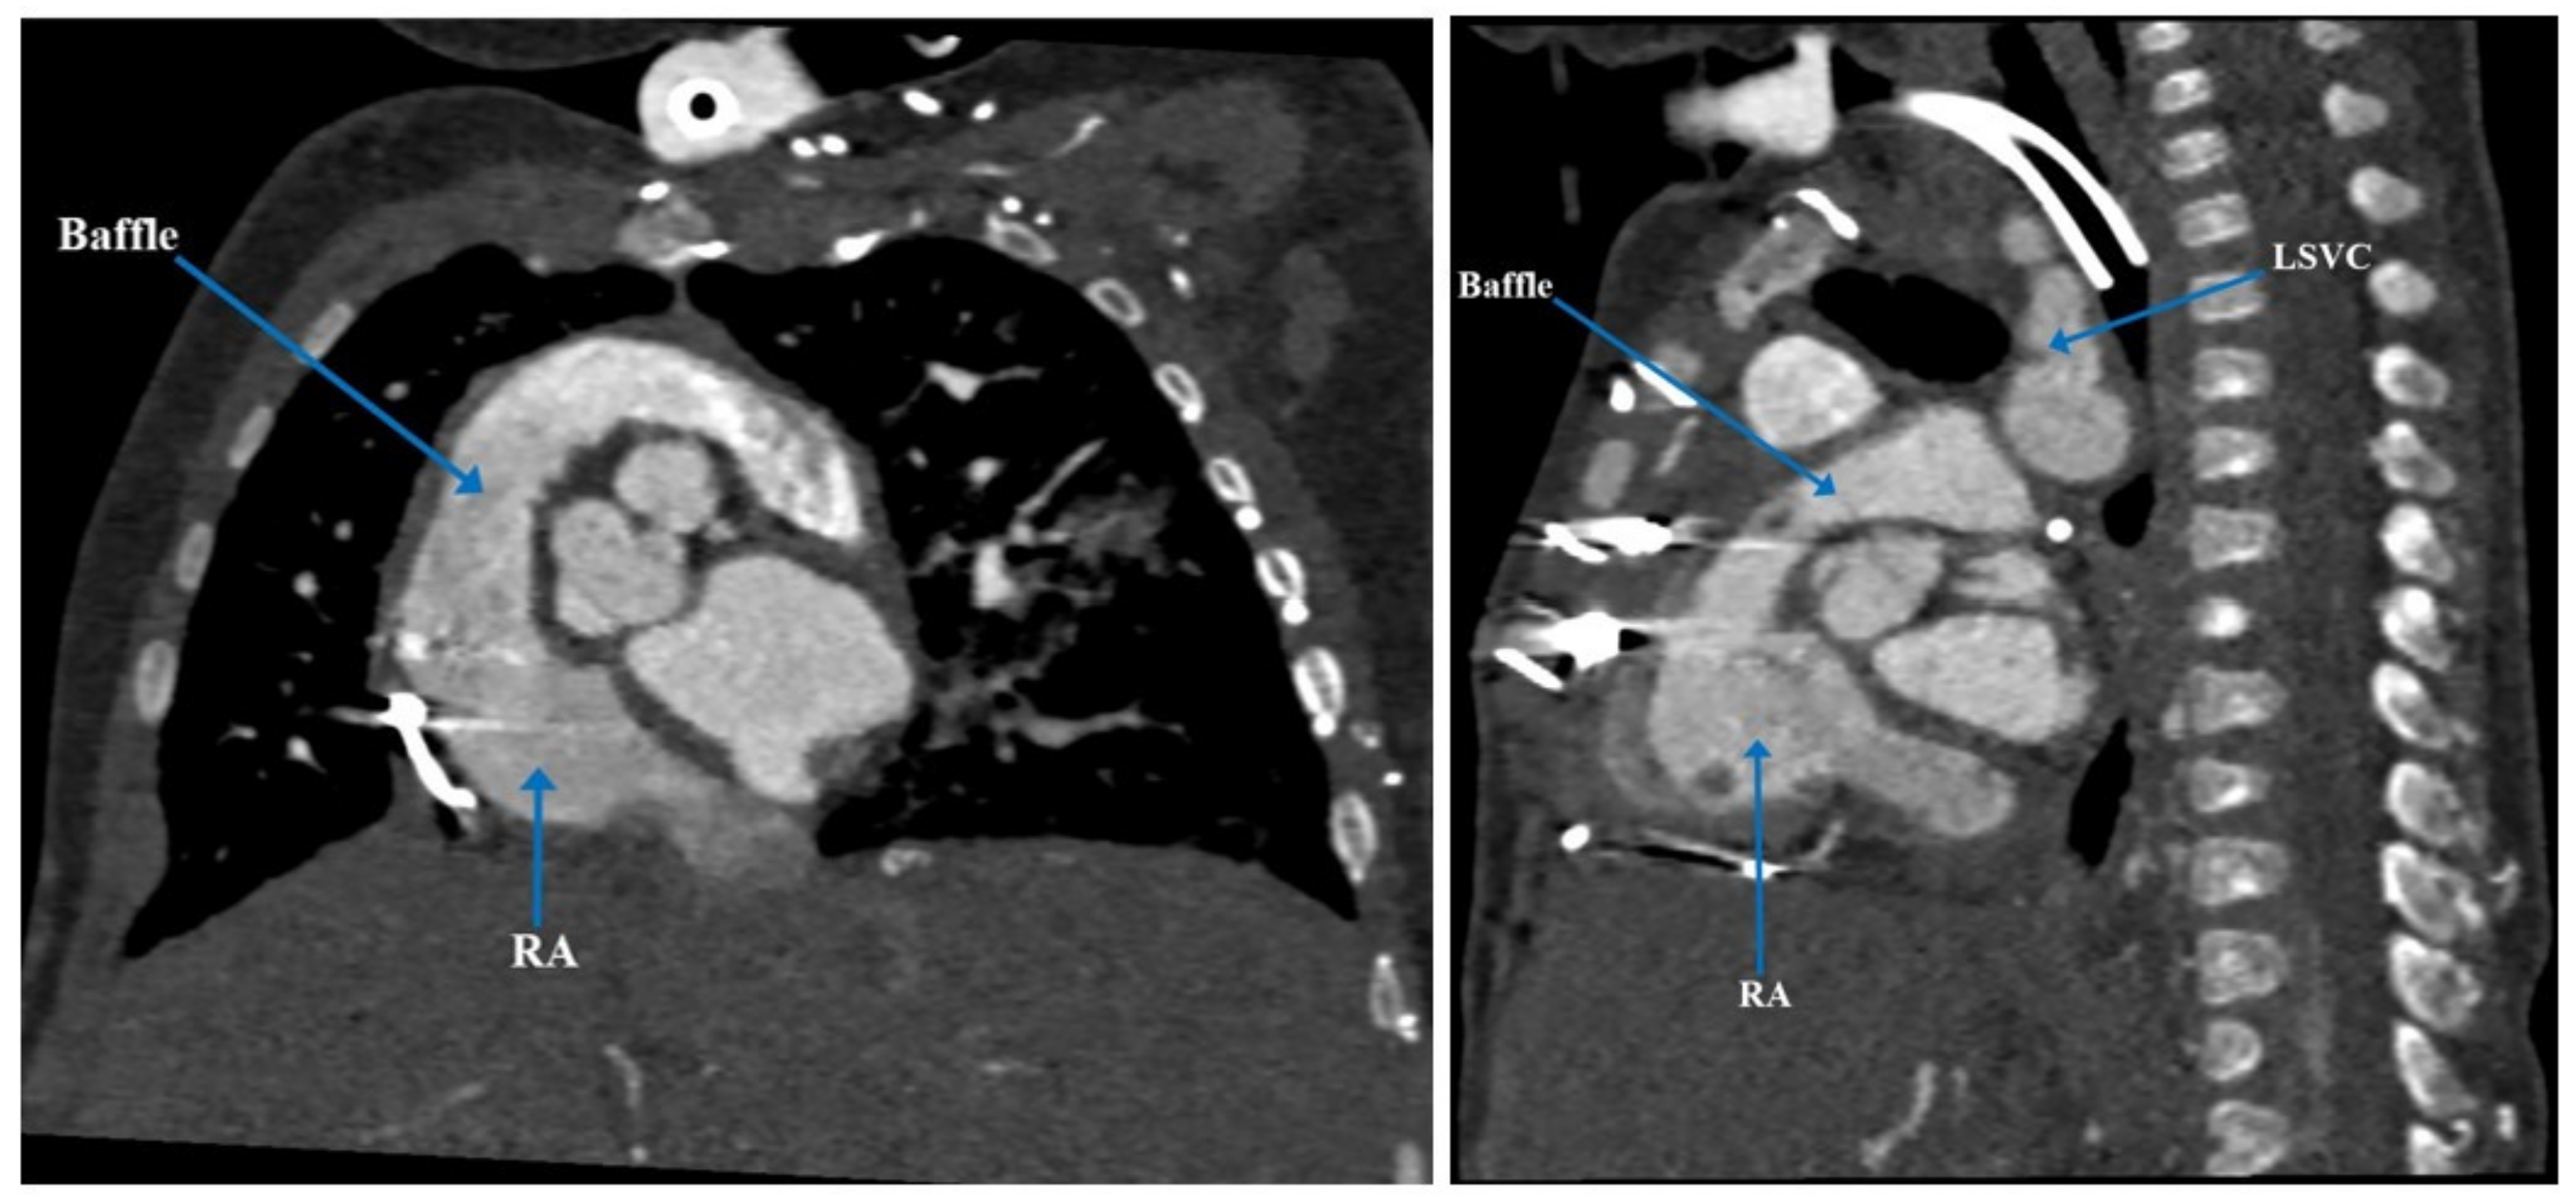

| Case 2: Heterotaxy syndrome, dextrocardia, isomerism of left-sided atrial appendages, bilateral SVCs, interrupted IVC with azygos continuation | 34 years | Septation of common atrium with two patch technique at 2 years and 34 years | Biventricular repair with atrial septation, redirection of systemic flow to tricuspid valve and pulmonary venous flow to mitral valve | ||

| Present case [6] | Heterotaxy syndrome with partial LPA sling, partial AV canal with a common atrium, atrial situs ambiguous, interrupted IVC, VSD, and PDA | 5 months | PDA occlusion, clipping and division of the anomalous LPA | Defined complex anatomy and surgical plan for biventricular repair | Biventricular repair |